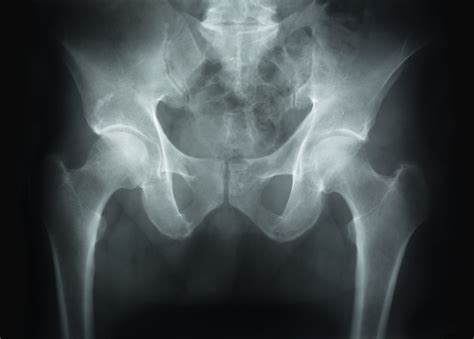

Avascular necrosis (AVN), also known as osteonecrosis, is a complex and often debilitating condition that occurs when the blood supply to a bone is disrupted. Without a steady supply of oxygen-rich blood, bone tissue begins to die, eventually leading to the collapse of the bone structure. Because early intervention is critical to preserving joint function and preventing long-term disability, recognizing Avascular Necrosis Symptoms is the most important step in the treatment process. This condition most commonly affects the hip, but it can also manifest in the knee, shoulder, ankle, and wrist.

Since the condition often starts invisibly, physicians use advanced imaging to confirm the presence of bone death. X-rays are typically the first line of defense, though they often fail to show early-stage damage. An MRI scan is widely considered the gold standard for diagnosing avascular necrosis, as it can detect changes in the bone marrow before the structure of the bone actually changes.